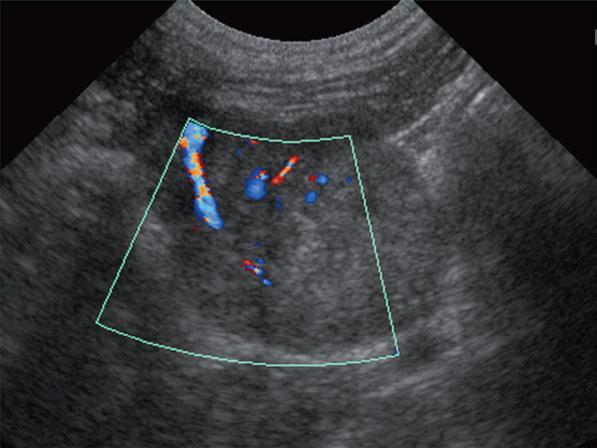

Badanie wykonano u 12-letniej, kastrowanej samicy owczarka australijskiego z prawostronną masą w dobrzusznej części szyi. Badanie USG wykazało dużą, litą, unaczynioną masę w obrębie prawego płata tarczycy (a) oraz mniejszą, hipoechogeniczną masę w obrębie lewego płata (b). Obrazy TK przed i po podaniu środka kontrastowego (c–f) ułożone od doczaszkowych do doogonowych ukazują dużą, prawostronną, jednorodnie wzmacniającą się masę (c–f – duża strzałka) z niewyraźną granicą dobrzuszną oraz pozatorebkowym szerzeniem się i rozlanym wzmocnieniem pokontrastowym przyległych tkanek (e, f – grot strzałki). W obrazie bardziej doczaszkowym widoczny jest prawidłowy lewy płat (c, e – mała strzałka), natomiast w obrazie bardziej doogonowym jest on powiększony i ma niższą gęstość, niż można by oczekiwać, co sugeruje obecność drugiej, mniejszej masy (d, f – mała strzałka). W obrazach reformowanych wzdłuż osi długiej widać dwa małe guzki w lewym płacie (h – małe strzałki). Wyniki obrazowe potwierdzono podczas zabiegu (i, j – strzałki). Biopsja wycinkowa wykazała prawostronnego raka tarczycy z naciekaniem pozatorebkowym oraz lewostronnego gruczolaka tarczycy